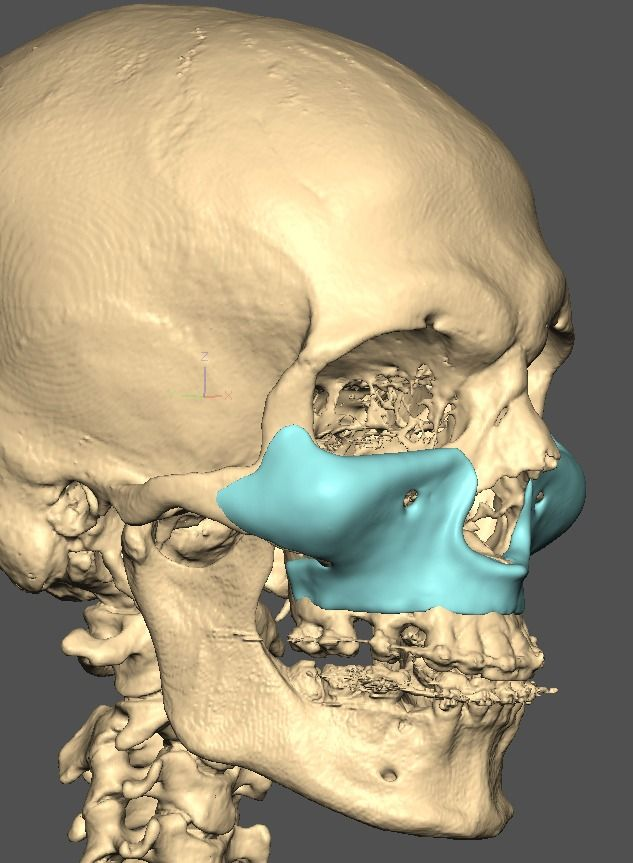

I know a guy who designed this for himself in collaboration with an asian implant company.

Not the final product yet, he is making adjustments as we speak.

Found a surgeon willing to insert it.

Giant and Eppley were the inspiration